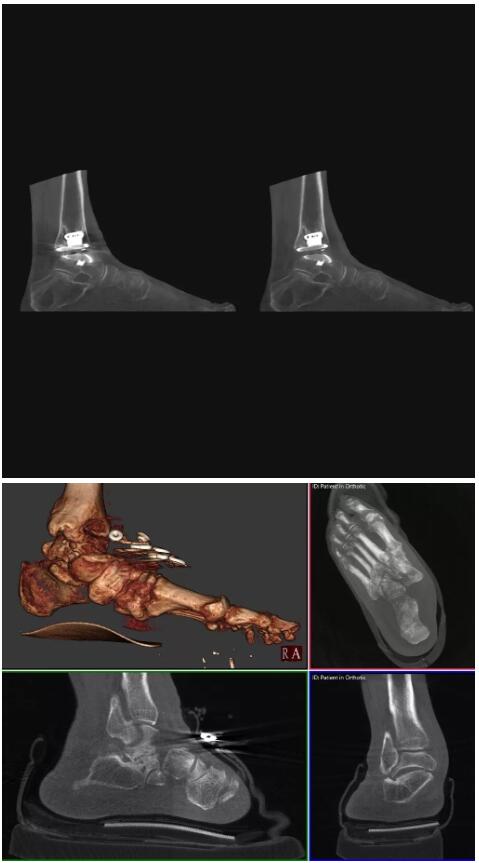

而患者站著做足部或者踝部做CT檢查還有個好處是,可以檢查患者在負(fù)重的情況下,骨關(guān)節(jié)的真實情況,而躺著做CT掃查時未必能看出來。負(fù)重CT掃查特別是對于受傷的運動員或者舞蹈員來說意義更大,能夠更準(zhǔn)確地評估傷情,幫助他們盡早復(fù)原。

以上介紹的CT均來自國外同一家公司,這些CT均配置了可視化軟件,可以進(jìn)行切片、3D重建以及大型CT附帶的所有典型的操作功能。

以下是這些“特立獨行”的CT所拍出來的圖像: